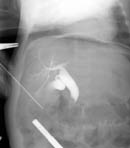

Таким образом, дооперационная диагностика кистозной трансформации желчевыводящих путей в настоящее время значительно улучшилась благодаря применению современных методов исследования. Однако, выбор оперативного метода лечения окончательно может быть произведен только во время операции, так как решающее значение в верификации диагноза имеют интраоперационные рентгеноконтрастные методы исследования, которые позволяют выявить кистозные расширения вне- и внутрипеченочных желчных протоков, степень и протяженность их дилятации, проходимость терминального отдела холедоха, рубцовые сужения печеночных протоков, билиопанкреатический рефлюкс. Поэтому всем больным после лапаротомии производилась интраоперационная холангиография и, на основании полученных данных решался вопрос о выборе метода хирургического лечения. Данная методика выполнена 10 пациентам (Рис. 3).

Рис. 3. Интраоперационная холангиография.